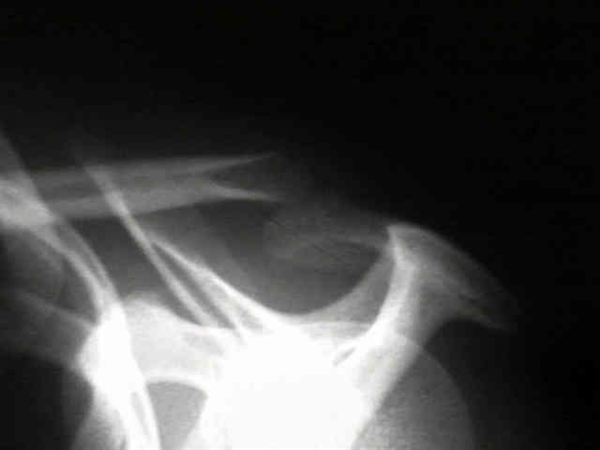

• Radiographs

• initial views

• AP +/- Zanca (for intra-articular injury)

• axillary lateral to define a Type-IV injury

• later findings

• intact periosteal sleeve forms a "new" lateral clavicle inferior to the superiorly displaced medial fragment.